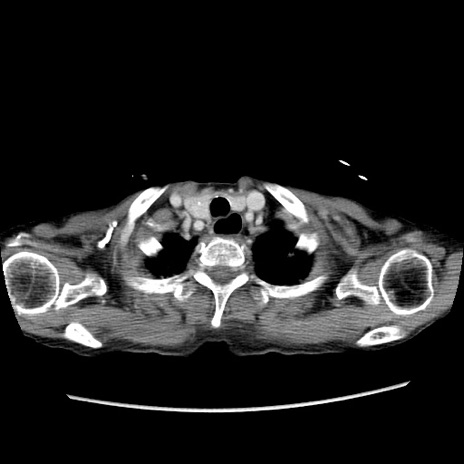

症例25(横断像)

【症例】80歳代女性

【主訴】胸のつかえ感

【現病歴】約9時間前に食後から胸のつかえた感じあり、嘔吐あり、来院。

【既往歴】胃癌(全摘)、胆摘、虫垂炎

【身体所見】心窩部に圧痛あり、反跳痛なし。

【データ】WBC 5700、CRP 0.05